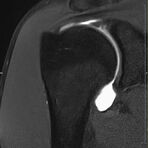

- Beurteilung von Knochen, Bändern und anderen Weichteilstrukturen der Gelenke nach Unfall.

- Arthrosediagnostik (Knorpelschaden)

- Impingement-Symptomatik

- Ursachenklärung bei wiederholter spontaner Gelenkluxation

- Ausbreitungsdiagnostik bei Gelenkentzündung, z.B. im Rahmen von rheumatischen Grunderkrankungen

- MR-Arthrographie – nach örtlicher Betäubung und gründlicher Desinfektion der Haut wird unter Lagekontrolle mit Röntgen-Durchleuchtung eine kleine Nadel in den Gelenkraum positoniert und darüber ein MR-taugliches Kontrastmittel in den Gelenkraum gespritzt. Danach wird die Nadel entfernt. Anschließend erfolgt die MRT des Gelenkes. Diese Methode stellt kleine anatomische Strukturen des Gelenkraumes verbessert dar, z.B. zur Therapieplanung vor Arthroskopie bei Sportverletzungen der Schulter oder Gelenkinstabilität.